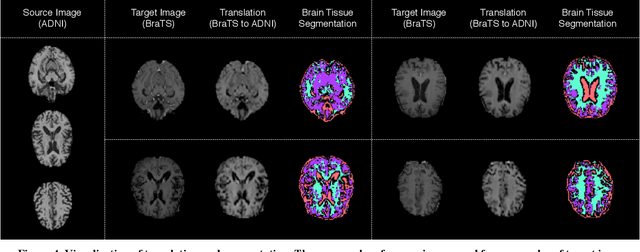

Abstract:With recent advances in supervised machine learning for medical image analysis applications, the annotated medical image datasets of various domains are being shared extensively. Given that the annotation labelling requires medical expertise, such labels should be applied to as many learning tasks as possible. However, the multi-modal nature of each annotated image renders it difficult to share the annotation label among diverse tasks. In this work, we provide an inductive transfer learning (ITL) approach to adopt the annotation label of the source domain datasets to tasks of the target domain datasets using Cycle-GAN based unsupervised domain adaptation (UDA). To evaluate the applicability of the ITL approach, we adopted the brain tissue annotation label on the source domain dataset of Magnetic Resonance Imaging (MRI) images to the task of brain tumor segmentation on the target domain dataset of MRI. The results confirm that the segmentation accuracy of brain tumor segmentation improved significantly. The proposed ITL approach can make significant contribution to the field of medical image analysis, as we develop a fundamental tool to improve and promote various tasks using medical images.